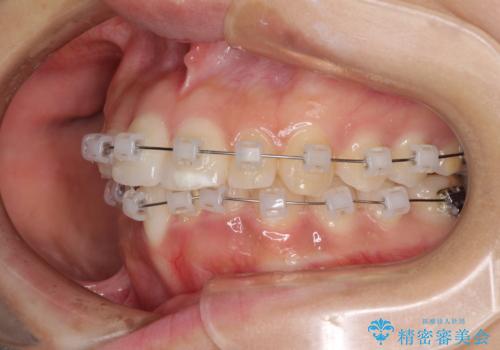

- クリアブラケット

大きなトラブルもなく、順調に歯列が整ったため、僅か9ヶ月で装置を外すことができました。

あまりに短期間であったため、患者様自身も非常に驚いていらっしゃいました。